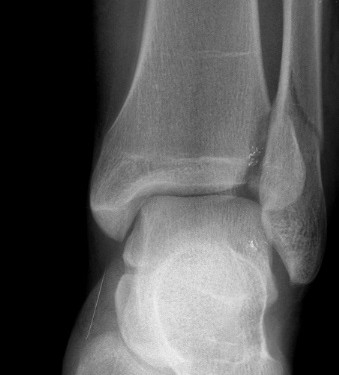

Ekstremite Kırıkları Distal tibia ve fibula kırığı

Distal tibia ve fibula kırığı